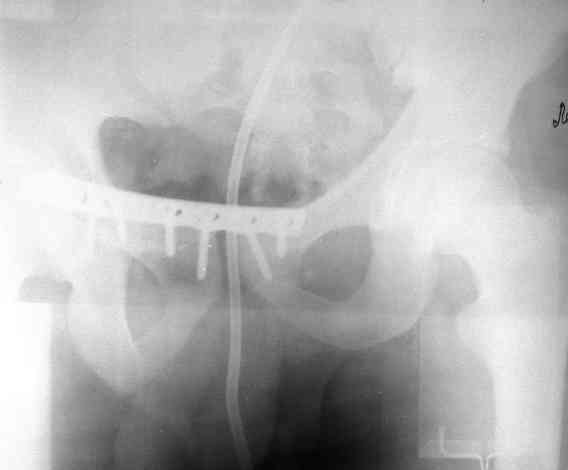

Уважаемые коллеги! На днях оперировал перелом таза месячной давности - разрыв симфиза, перелом обеих ветвей правой лонной кости, трансфораминальный перелом крестца слева. Представляю рентгенограммы с задержкой - технические причины.

Предоперационные рентген и КТ, в операционной - снимки после каждого фиксатора. Вертикальное смещение полностью устранить не удалось. В первую очередь за счет заднего полукольца. Хотя при компрессии на стержнях горизонтальное смещение было сантиметра 1,5. Т.е. крестец, на мой взгляд еще не сросся. От коллег хотел-бы услышать допустима-ли такая остаточная деформация?